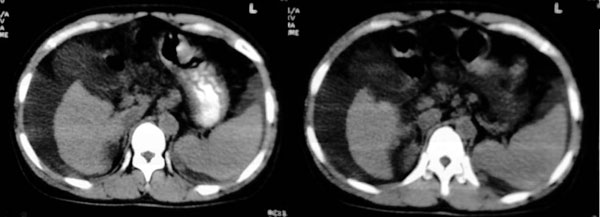

患者:女,43岁,自觉全身肿胀8个多月。b超提示:肝硬化、腹水,胆囊炎。胰、脾、肾未见明显异常。

肝脏形态不正常,比例失调,肝裂增宽,应该是肝硬化、腹水、脾脏稍大。

肝脏体积变小,左右比例失调,右肝变小较剧,脾脏增厚,腹水征象明显考虑肝硬化、腹水

大家好,还有就是她的胆囊在哪?那肝右前间隙液体内环状稍高密度是什么,又为什么壁欠光滑.请大家再帮忙看看.